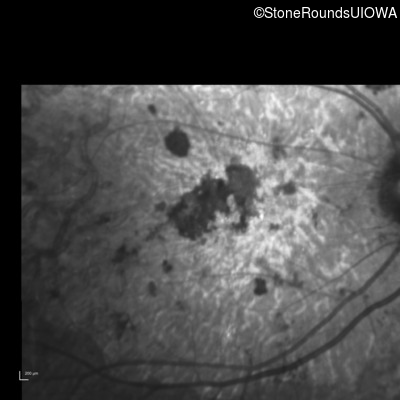

Infrared Fundus Photograph - Right - 20/250 sc

Exemplar